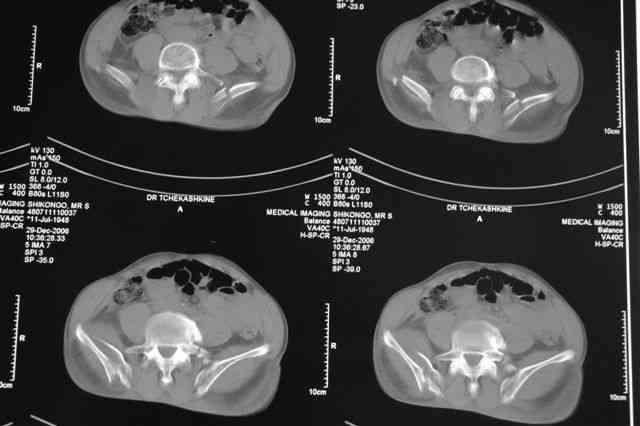

В приложении отправляю послеопер. снимки бедра и лодыжки обсуждаемого вчера больного.

В приложении послеоперационные картинки.